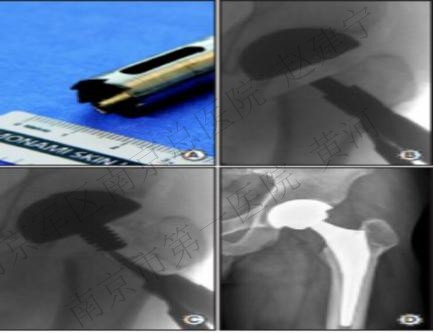

(5)钽棒

目的:髓芯减压的基础上提供股骨头软骨下的结构支持,钽棒的多孔表面能够促进骨的长入,避免股骨头进一步的塌陷,无需植入自体或异体骨。

病人的选择:早期,无股骨头塌陷,ARCO I期或II期的患者。

早期的报道较为乐观,Veillete对44例患者的随访发现,24个月时股骨头存活率达91.8%,但48个月时的存活率降到68.1%。近年来质疑增加,Floerkemeier随访发现钽棒治疗并不比单纯髓芯减压的疗效更好,Tanzer在对钽棒植入后失败的患者行关节置换时发现,钽棒的多孔结构并未使骨长入增多,软骨下的的力学支持也不尽如人意。

Lee则探讨了钽棒植入失败后关节置换可能存在的困难,包括钽棒取出困难、易造成股骨近端骨折、增加手术时间、增加术中及术后的出血、难以清除的金属残留、造成股骨外侧皮质的缺损,等等。

A 钽棒取出装置;B 连同钽棒自股骨颈部切断;C 顺行将残留钽棒打出;D 关节置换术后X片显示外侧皮质缺损。

A 逆行取出钽棒;B 环锯沿钽棒扩钻,产生大量金属颗粒(箭头);C 关节置换术后X片显示粗隆骨折,环扎固定。